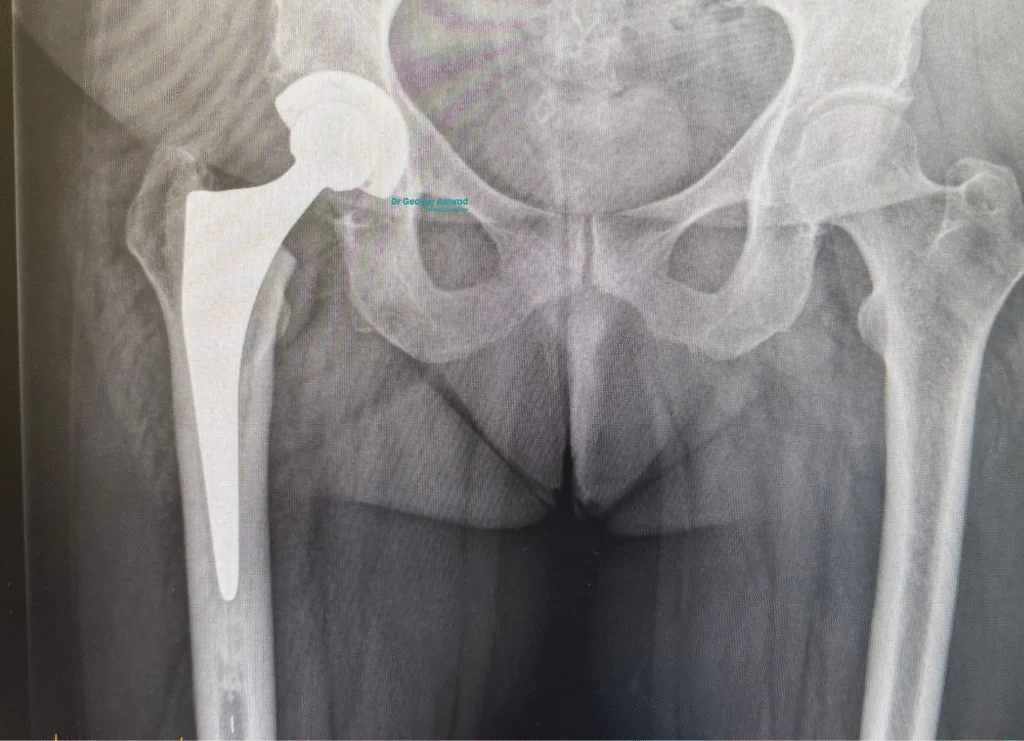

During a total hip replacement, the damaged parts of the hip joint are replaced with prosthetic components designed to restore function, reduce pain, and support long-term mobility. Dr Awwad selects each implant based on your unique anatomy, lifestyle, and long-term goals.

Main components of a hip replacement

A typical total hip replacement involves three key components:

- Acetabular cup – This replaces the hip socket. It is usually made of a strong metal and contains a smooth inner liner made of polyethylene or ceramic, allowing the joint to move freely.

- Femoral stem– Inserted into the thigh bone (femur), this metal component provides the foundation for the artificial joint. Stems come in various shapes and sizes to match the patient’s bone structure.

- Femoral head – The ball component fits into the socket and mimics the natural head of the femur. It may be made of ceramic or metal, depending on individual needs.